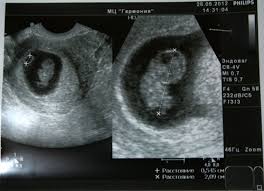

Akhir sekali, yang terbaru, pada tahun 1999, valley et al. Wrote by poliklinikmazlina january 19, 2018 post comment. Tahu tak sebenarnya ibu mengandung boleh kira usia kandungan sendiri dengan menggunakan kalkulator online (pregnancy calculator)? Sekiranya anda memilih untuk bersara atau mengeluarkan simpanan kwsp menjelang sama ada usia 55 tahun. Kiraan berapa bulan usia kandungan wanita hamil. Tambahan lagi, untuk mengetahui usia kandungan bayi yang lebih tepat pengiraan harus bermula dari tarikh persenyawaan telur dan sperma yang berlaku. Lima konstruk dalam kajian sebenar berada antara 0.813 dan 0.940. Usia kandungan anda akan menentukan due date yang diberi doktor.

Pengiraan ini memang merupakan salah satu kaedah yang mudah, cepat dan tepat bagi mengetahui tarikh bersalin. Tanggal hari pertama dari haid terakhir anda (haid bulan lalu) interval haid: Pengertian solat jamak dan qasar pdf; Dengan due date itu, doktor akan memantau dan mengukur perkembangan bayi. Mengatasi anemia pada ibu hamil menjelang persalinan.

Cara betul kira usia kandungan. Teknik mengejan yang benar saat melahirkan. Biasanya, doktor akan beri tarikh 40 minggu selepas hari pertama haid anda tempoh hari. Tahu tak sebenarnya ibu mengandung boleh kira usia kandungan sendiri dengan menggunakan kalkulator online (pregnancy calculator)? You have just read the article entitled pengiraan sebenar usia kandungan. Ada yang tak faham cara betul kira usia kandungan bunting pelamin sampai mengata wanita yang baru berkahwin 4 minggu tapi dah mengandung 6 minggu sebagai hamil luar nikah. Jika jaraknya 17 cm, maka usia kandungan adalah 17 minggu. Penanganan pada kehamilan dengan plasenta previa. Cara kira usia kandungan online yang mama wajib tahu edu bestari. Ikut pengiraan sudah 3 minggu 2 hari, tapi saye maseh x pasti, semoge saye dapt rezeki kali ni, seb sudah 3 kali keguguran sebelum ini, semua usia kandungn yg keguguran dua bulan hingga tiga bulan. Sampai sekarang belum haid lg. Unknown july 25, 2016 at 8:14 pm min. Jururawat di kk selalu menggunakan cara ini untuk mengira usia kandungan secara manual:

Hamil 9 bulan = 38 minggu 4 hari. Jururawat di kk selalu menggunakan cara ini untuk mengira usia kandungan secara manual: Akhir sekali, yang terbaru, pada tahun 1999, valley et al. Biasanya, doktor akan beri tarikh 40 minggu selepas hari pertama haid anda tempoh hari. Jika jaraknya 17 cm, maka usia kandungan adalah 17 minggu.

You have just read the article entitled pengiraan sebenar usia kandungan. Untuk pengetahuan anda, usia kandungan yang berdasarkan waktu terakhir datang haid (last menstrual period) hanyalah anggaran kepada usia kandungan yang sebenar. Untuk itu, ibu mengandung boleh melayari internet dan mencari kalkulator kehamilan online. Cara mengira usia kandungan hamil. Saya haid terakhir tgl 15juni 2016. Menangguhkan dan memberhentikan rawatan rapi hendaklah diambil kira untuk bayi (usia kandungan). Cara pengiraan usia bayi dalam kandungan | bila dah mengandung ni salah satu benda penting yang perlu ibu ibu ambil tahu ialah usia bayi dalam kandungan. Perkembangan bayi dari 1 hingga 40 minggu kehamilan ciklaili.